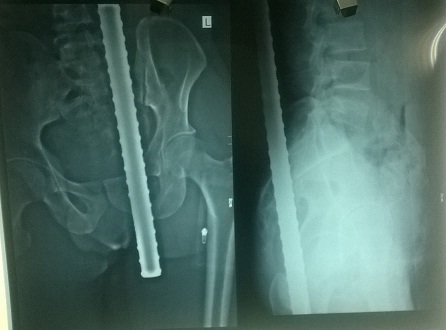

Hình ảnh X-quang cho thấy rõ, thanh sắt đâm xuyên từ thắt lưng xuống tầng sinh môn bệnh nhân |

Theo BS. Khiết, qua thăm khám ban đầu, bệnh nhân không có dấu hiệu liệt hai chi dưới, không có dấu hiệu tổn thương mạch máu. Kết quả hình ảnh chụp X-quang thấy rõ hình ảnh dị vật đâm xuyên từ thắt lưng xuống tầng sinh môn. Bệnh nhân nhanh chóng được đưa đi mổ cấp cứu. Kíp phẫu thuật đã làm việc tích cực, khẩn trương sau hơn 3 giờ đồng hồ phẫu thuật đã cứu sống bệnh nhân.